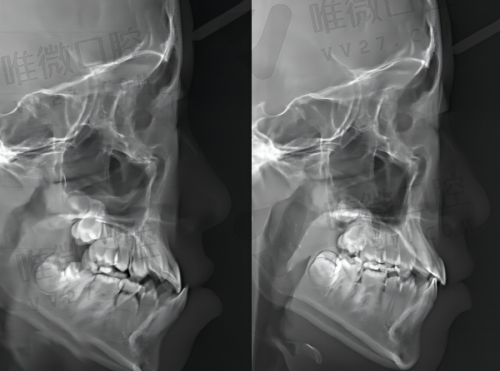

现代口腔治疗早已经进化成“智能牙科”时代了,光会看牙可不行,还得靠高新科技手段来提效率、保成效。上海雅洁口腔紧跟国内外新技术,引入了包括口腔CBCT、数字化扫描仪、瓷??滔低?、种植导板设计、一站式全瓷修复系统等设备,让看牙这件事不再靠“手艺”+“经验”硬撑。

像3D种植导板技术可以在种牙前通过数据建模确定植体角度、深度精度,大大提升种植成功几率,不至于“种了后悔”;全瓷牙冠可实现数字化快速制作,当天戴牙成为可行,让复诊次数降到较低。对于时间宝贵的白领或外地客户来说,这一点非常友好。

高新科技让牙齿治疗更精细、更安心。例如拔智齿前可做CBCT定位神经走向、更精细评估手术风险,隐形矫正还能模拟更终成效,提前“看见”新牙型,大大降低消费顾虑。